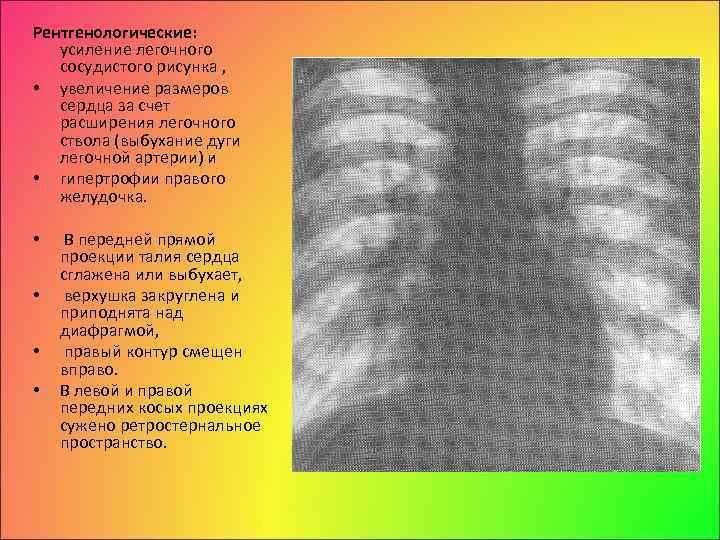

Усиление сосудистого рисунка легких у ребенка может быть признаком различных патологий и состояний. Это визуальное изменение на рентгеновских снимках обычно связано с увеличением притока крови в сосуды легких, что может указывать на наличие воспалительных процессов, инфекций или аллергических реакций. Также это наблюдается при повышении давления в легочной артерии, что может быть вызвано сердечными заболеваниями или другими патологиями системы кровообращения. В любом случае, обнаружение усиленного сосудистого рисунка легких у ребенка требует дополнительного обследования и консультации с педиатром или пульмонологом для постановки точного диагноза и назначения соответствующего лечения.